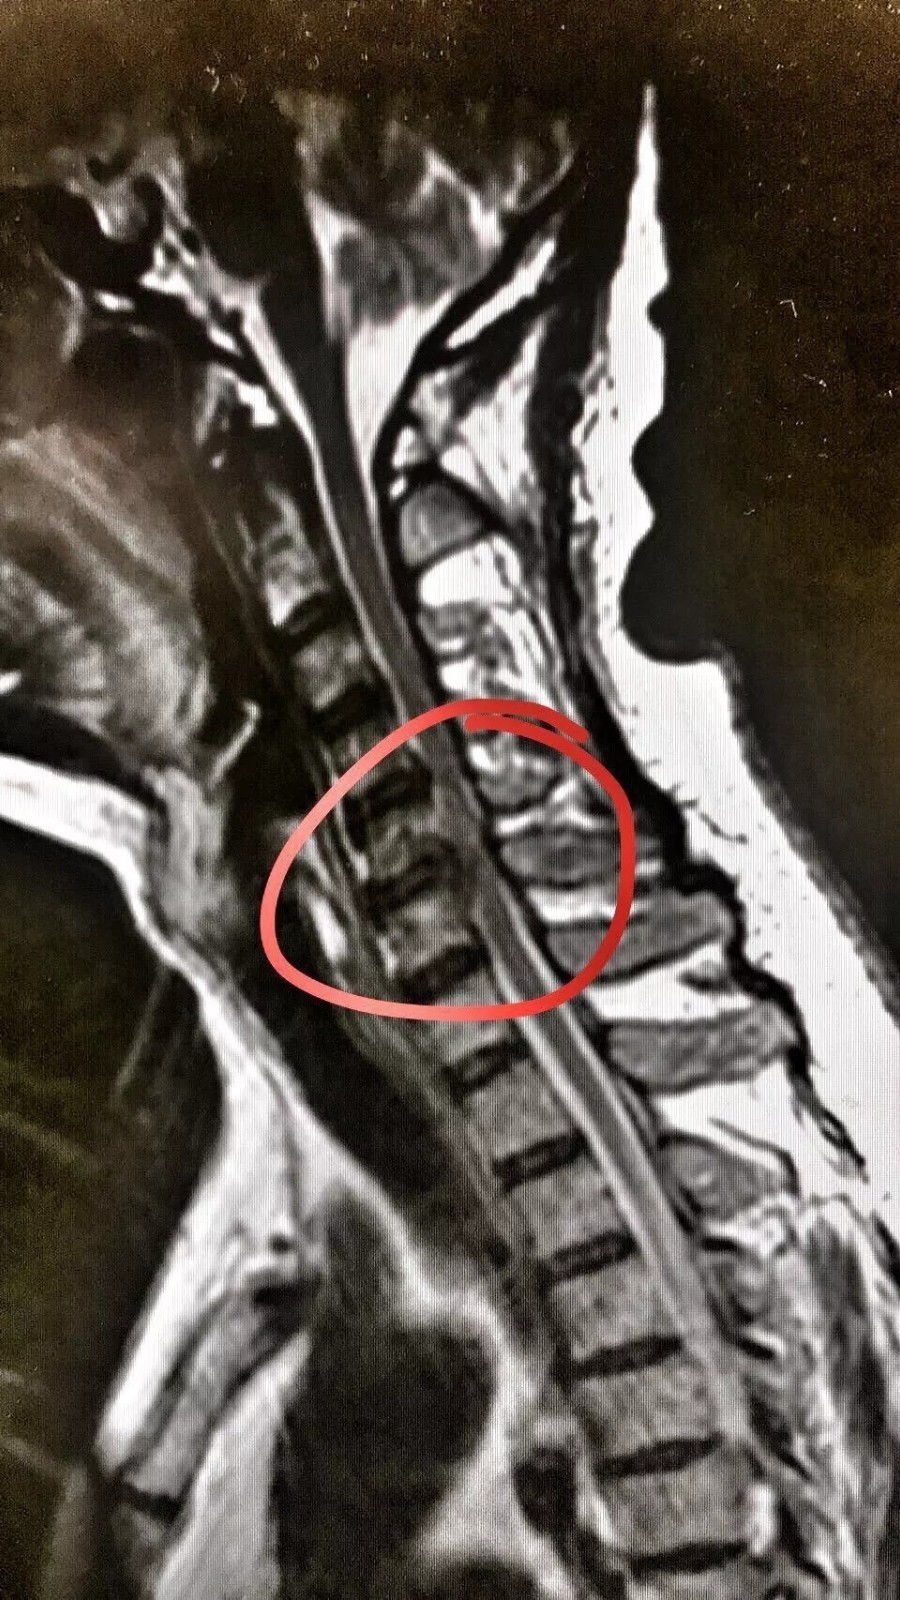

椎间序列关系正常,颈3/4.4/5椎间盘局限向后正中超出椎缘,硬膜囊危险性大吗,术后会有后遗症吗,我很担心